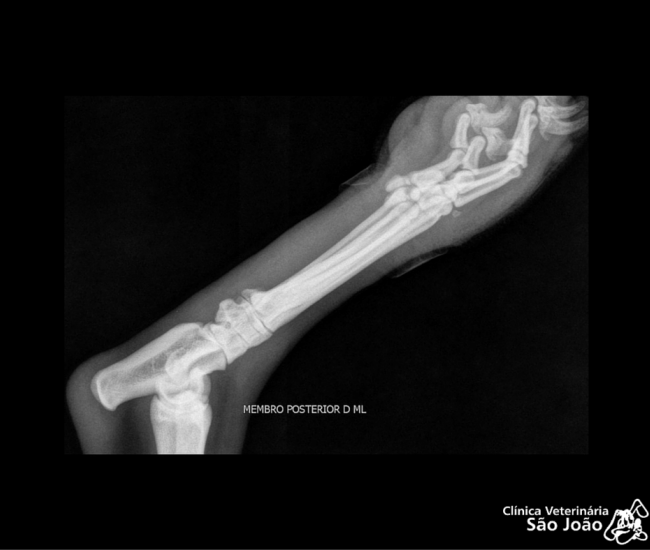

- Diferentemente do raio-x analógico, este raio-x oferece altíssima definição e todas as vantagens da tecnologia digital. É possível aproximar a imagem, trabalhar o contraste, exposição.O software permite ainda avaliações da medida cardíaca do animal e graus de displasia coxofemoral, por exemplo – explica o Dr. Nardeli Lucena.

O raio-x digital possibilita ainda a redução da radiação a que o animal deve ser exposto e também diminuição no tempo de duração do exame. O que se torna muito vantajoso tanto para o animal, quanto para o médico radiologista e para o acompanhante do animal ( que geralmente precisa permanecer na sala).

Outra importante vantagem da radiografia computadorizada é que ela é uma tecnologia limpa, que não gera resíduos. É possível imprimir o Raio-X digital, gravá-lo em um CD ou pen-drive, mas muitos veterinários, optam pelo  envio das imagens por e-mail, o que torna mais rápido o diagnóstico.